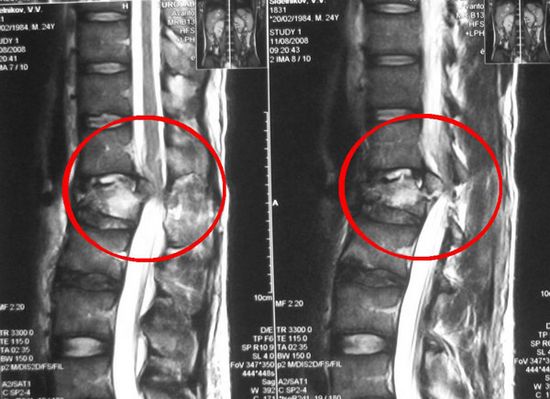

У лиц с легочным туберкулезом врачи выявляют заболевание легко. Для подтверждения диагноза они используют рентгенографию, КТ или МРТ. Немаловажное диагностическое значение также имеет обнаружение микобактерий в биоптате или гнойном отделяемом из свищей.

Признаки туберкулеза позвоночника

Поначалу человека беспокоит постоянная усталость, общая слабость и ночные боли в спине. Со временем болезненные ощущения усиливаются и начинают иррадиировать в другие части тела. При поражении шейного отдела позвоночника боль распространяется на шею и надлопаточную область, грудного – живот и грудную клетку, пояснично-крестцового – нижние конечности.

На поздних стадиях туберкулез позвоночника может сопровождаться образованием «холодных абсцессов». Чаще всего они располагаются на затылке, шее, бедрах, ягодицах, подвздошной области. Такие абсцессы не вызывают симптомов острого воспаления (болезненности, лихорадки, локального повышения температуры и покраснения кожи).

Туберкулез позвоночника нередко приводит к тяжелым осложнениям. К ним относятся пролежни, расстройства функций органов малого таза, парезы и параличи мышц нижних конечностей.